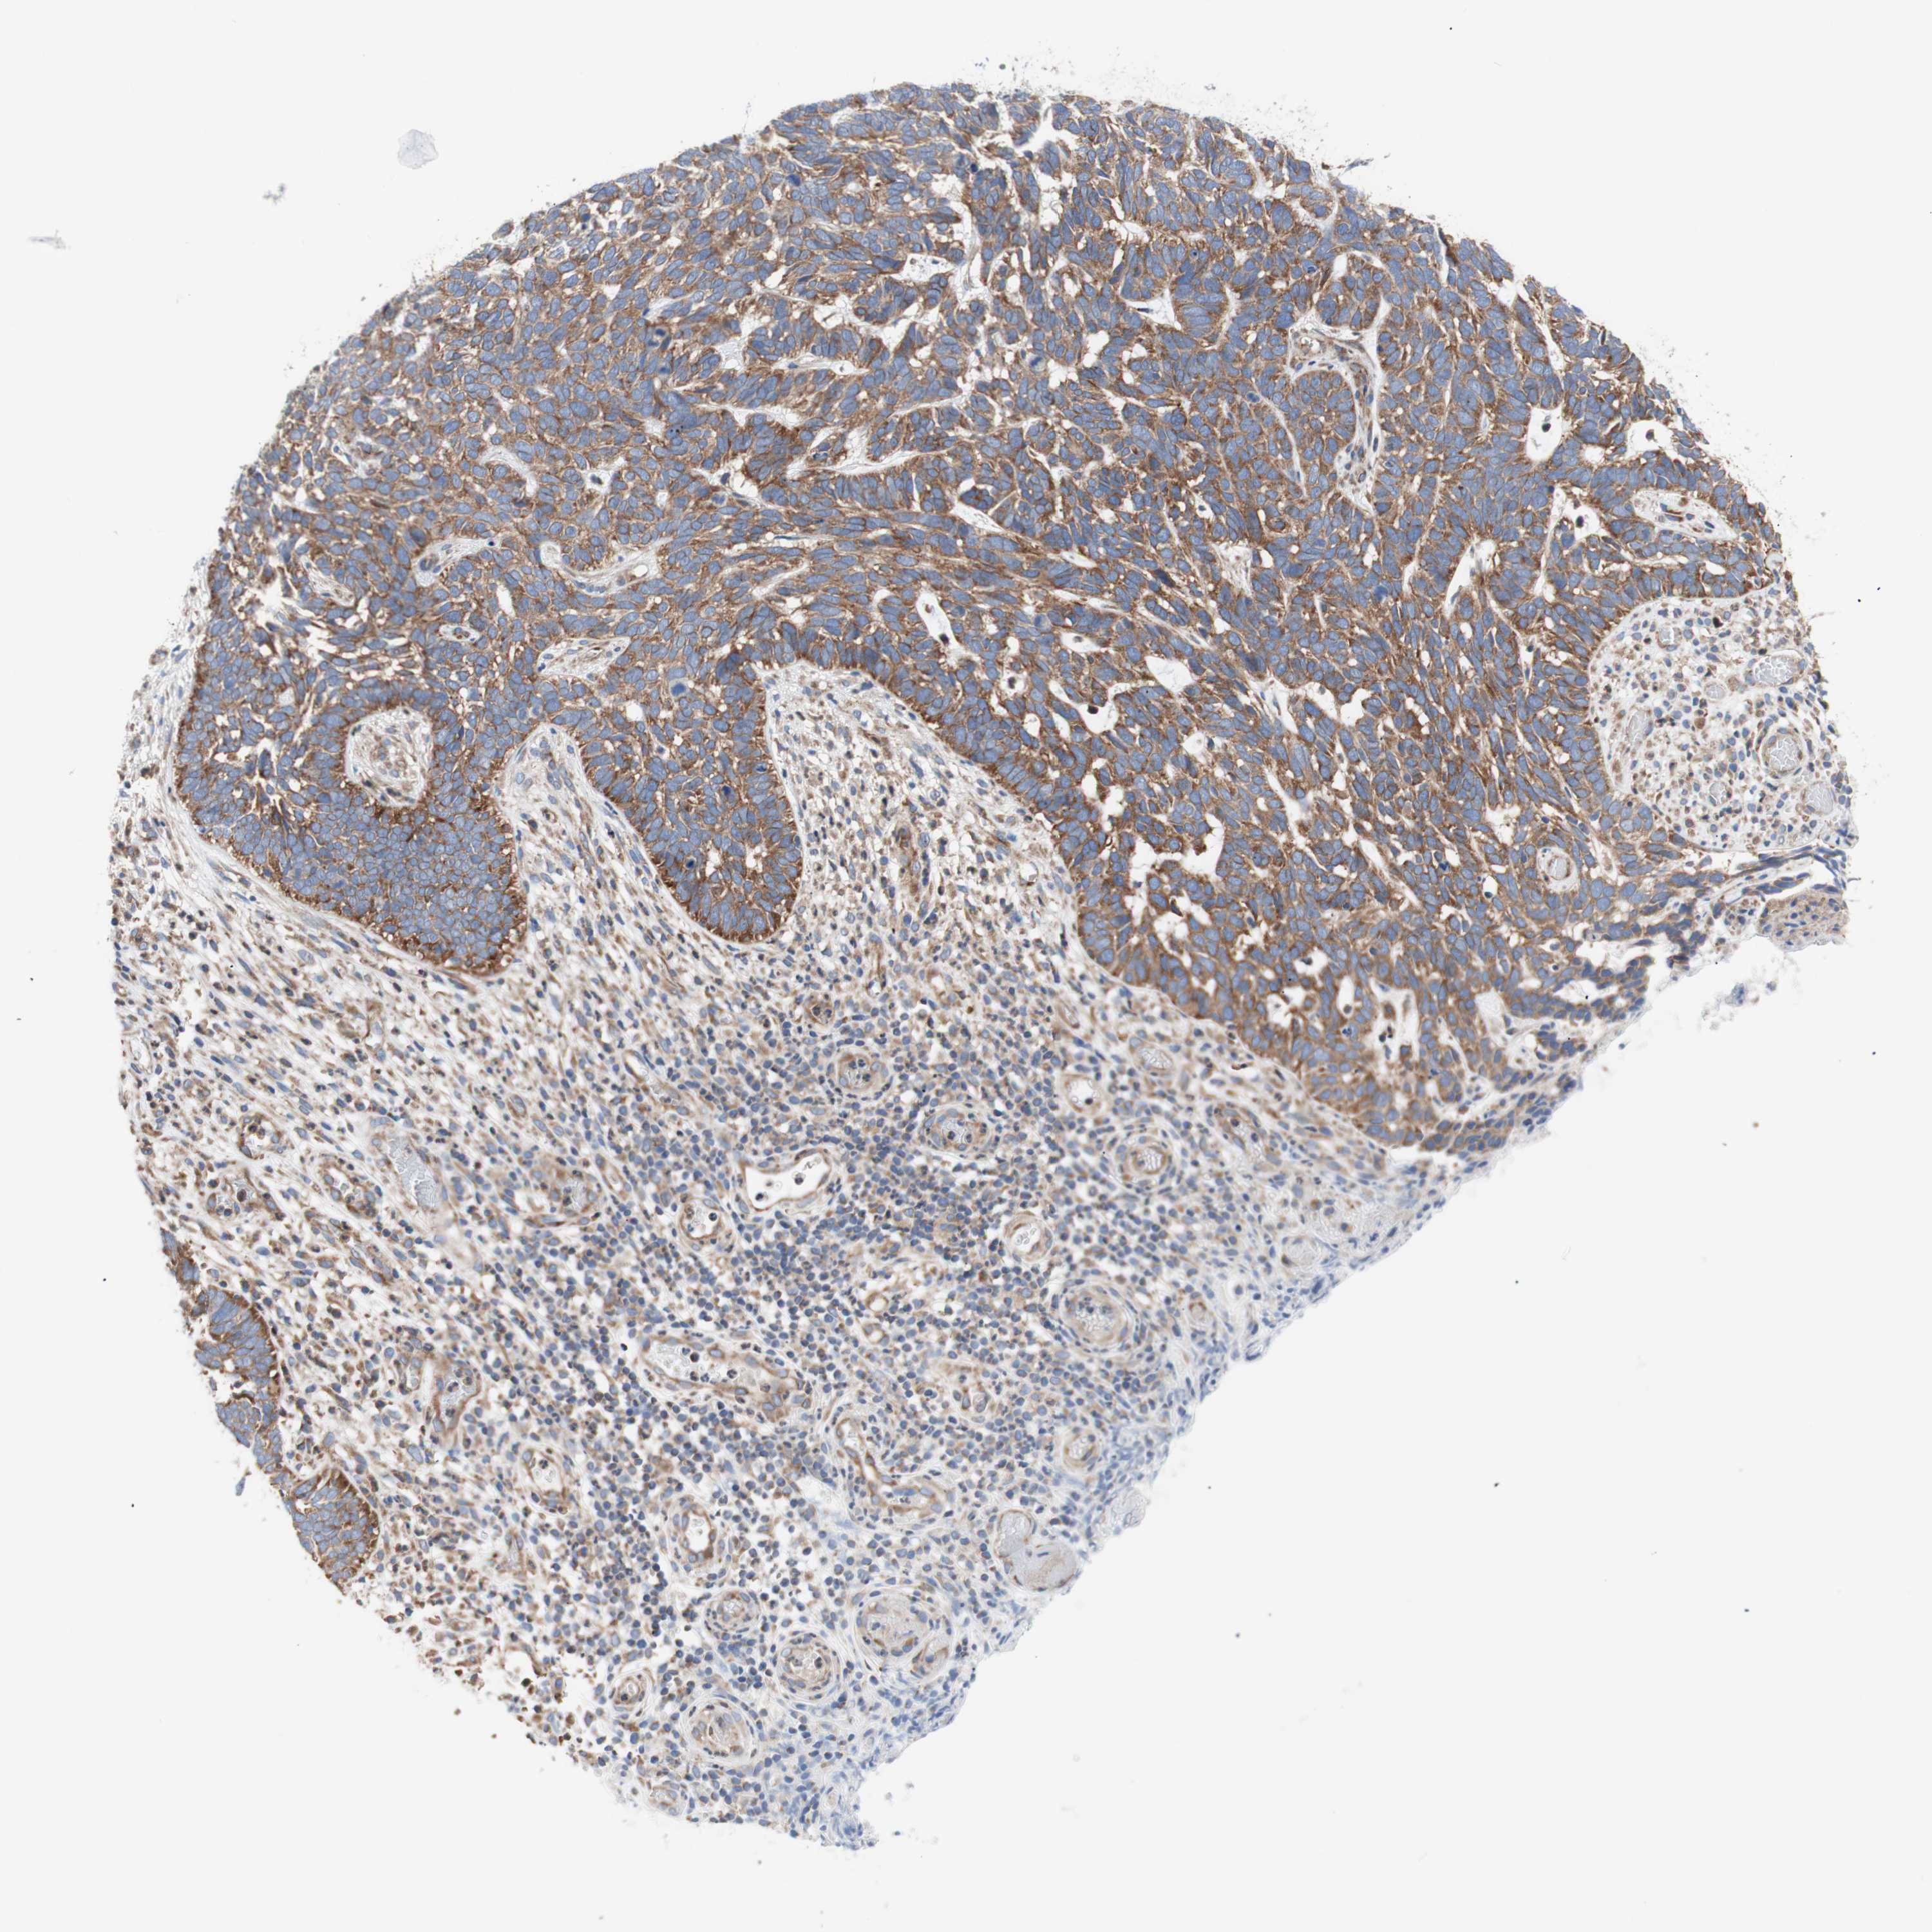

CANCER SKIN CANCER Show tissue menu

Basal cell and squamous cell cancer

SKIN CANCER - Protein expressioni

A mouse-over function shows sample information and annotation data. Click on an image to view it in a full screen mode. Samples can be filtered based on level of antibody staining by selecting one or several of the following categories: high, medium, low and not detected. The assay and annotation is described here.

Each image is clickable and will lead to virtual microscopy that enables deeper exploration of all samples and also displays staining intensity scores, fraction scores and subcellular localization as well as patient and tissue information for each sample.

Antibody HPA050118

Antibody HPA056084

Antibody CAB012444

Basal cell carcinoma

Squamous cell carcinoma, NOS

Squamous cell carcinoma, metastatic, NOS